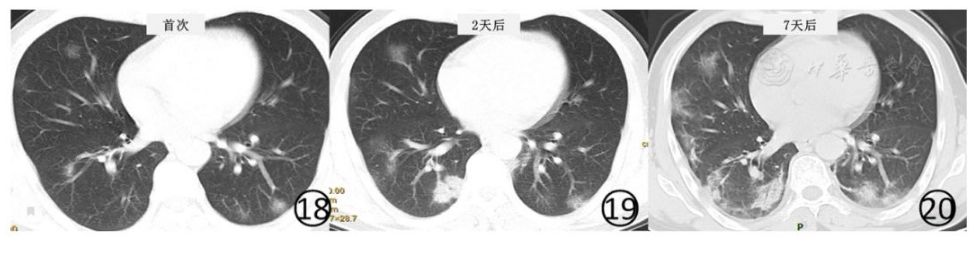

新冠肺炎影像表现进展

随着病情进展,病灶逐渐实变,影像学逐渐失去特异性,甚至成为“白肺”。我们正常人几乎可不能通过“白肺”看出来是新冠肺炎,普通的肺炎恶化都会形成“白肺”。

下面是影像学进展过程。

A.进展为实变。

图24

B.进展为白肺。

图25